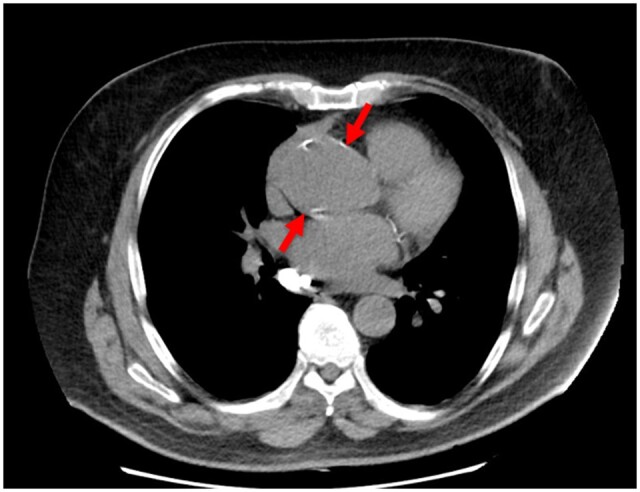

Objectives: This diagnostic study assessed the accuracy of radiologists retrospectively, using the deep learning and natural language processing chest algorithms implemented in Clinical Review version 3.2 for: pneumothorax, rib fractures in digital chest X-ray radiographs (CXR); aortic aneurysm, pulmonary nodules, emphysema, and pulmonary embolism in CT images.

Results: The missed findings were: 0.02% rib fractures, 0.51% aortic aneurysm, 0.32% pulmonary nodules, 0.92% emphysema, and 0.28% pulmonary embolism. The positive predictive values (PPVs) were: pneumothorax (0%), rib fractures (5.6%), aortic dilatation (43.2%), pulmonary emphysema (46.0%), pulmonary embolus (11.5%), and pulmonary nodules (9.2%). The PPV for pneumothorax was nil owing to lack of available studies that were analysed for outpatient activity.

Advances in knowledge: The diagnostic accuracy of our radiologists generated missed findings of 0.02% for rib fractures CXR, 0.51% for aortic dilatation, 0.32% for pulmonary nodule, 0.92% for pulmonary emphysema, and 0.28% for pulmonary embolism for CT studies, all retrospectively evaluated with AI used as a quality tool to flag potential missed findings. It is important to account for prevalence of these chest conditions in clinical context and use appropriate clinical thresholds for decision-making, not relying solely on AI.